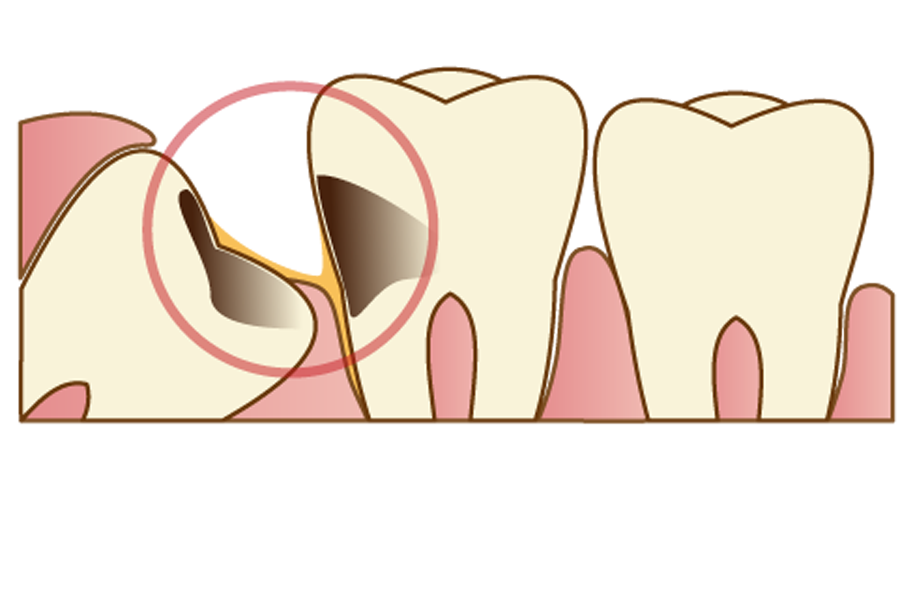

親知らず自体が、虫歯や歯周病になっている場合

親知らずがむし歯や歯周病になっている場合、まわりの健康な歯にも影響が及ぼんでしまう可能性がありますので、抜歯した方が良いでしょう。

ですが、親知らずがまっすぐに生えていて上下の歯とかみ合っており、かつ、むし歯や歯周病の症状が軽度の状態であれば、治療したうえで残すという判断をする場合もあります。